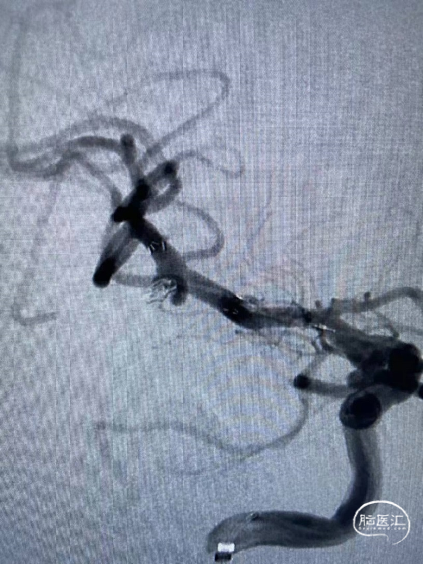

造影:左侧颈内动脉交通段动脉瘤支架辅助栓塞后改变,瘤体内无造影剂泻入,大脑中动脉及大脑前动脉走形正常,显影良好,左侧大脑前动脉A3段可见约2.0mm*1.5mm大小动脉瘤。右侧颈内动脉交通段可见约6.7mm*2.8mm大小动脉瘤,分叶状,瘤颈宽4.0mm,胚胎型大脑后动脉,右侧大脑中动脉M1段可见宽颈梭型动脉瘤,大小约3.9mm×4.6mm。

工作位+路图下Synchro-0.014in×200cm微导丝携带PROWLER SELECT PLUS微导管送至右侧大脑中动脉M2段远端,微导丝携带Echelon-10微导管送至M1段动脉瘤体内。经PROWLER SELECT PLUS微导管释放ENTERPRISE2 4.0mm×16mm,覆盖瘤颈,经Echelon依次填入强生ORBIT GALAXY 3mm×6cm弹簧圈成篮,继续填入ev3 2.5mm×6cm,1mm×2cm,1mm×1cm弹簧圈,造影示M1段动脉瘤填塞完全,造影剂滞留。

调整工作位角度,路图下Synchro0.014×200cmm微导丝携带SL-10微导管送至右侧颈内动脉,再用微导丝携带Echelon-10微导管送至C7动脉瘤瘤体内,经Echelon-10半释放强生ORBIT GALAXY 3mm×8cm弹簧圈,经SL-10释放Neuroform Altas 4.0mm×21mm支架,覆盖瘤颈,继续填塞第一枚弹簧圈,造影示支架位置满意,继续填塞强生ORBIT GALAXY 2mm×6cm弹簧圈,ev3 1mm×3cm,1mm×2cm弹簧圈,复查造影示动脉瘤栓塞致密,载瘤动脉通畅,复查颅内正侧位造影右侧颈内动脉、大脑前动脉、大脑中动脉显影良好。

复查:左侧颈内动脉C7段动脉瘤完全栓塞

右侧颈内动脉交通段可见约6.7mm*2.8mm大小动脉瘤,分叶状,瘤颈宽4.0mm

右侧大脑中动脉M1段可见宽颈梭型动脉瘤,大小约3.9mm×4.6mm,左侧大脑前动脉A3段可见约2.0mm*1.5mm大小动脉瘤。

路图下Synchro0.014×200cm微导丝携带PROWLER SELECT PLUS微导管送至右侧大脑中动脉M2段远端,微导丝携带Echelon-10微导管送至M1段动脉瘤体内。

经PROWLER SELECT PLUS微导管释放ENTERPRISE2 4.0mm×16mm,覆盖瘤颈,经Echelon依次填入强生ORBIT GALAXY 3mm×6cm弹簧圈成篮,继续填入ev3 2.5mm×6cm,1mm×2cm,1mm×1cm弹簧圈,造影示M1段动脉瘤填塞完全,造影剂滞留。

路图下Synchro0.014×200cmm微导丝携带SL-10微导管送至右侧颈内动脉,再用微导丝携带Echelon-10微导管送至C7动脉瘤瘤体内,经Echelon-10半释放强生ORBIT GALAXY 3mm×8cm弹簧圈,经SL-10释放Neuroform Altas 4.0mm×21mm支架,覆盖瘤颈。

造影示支架位置满意,继续填塞强生ORBIT GALAXY 2mm×6cm弹簧圈,ev3 1mm×3cm,1mm×2cm弹簧圈,复查造影示动脉瘤栓塞致密,载瘤动脉通畅。

造影右侧颈内动脉、大脑前动脉、大脑中动脉显影良好。